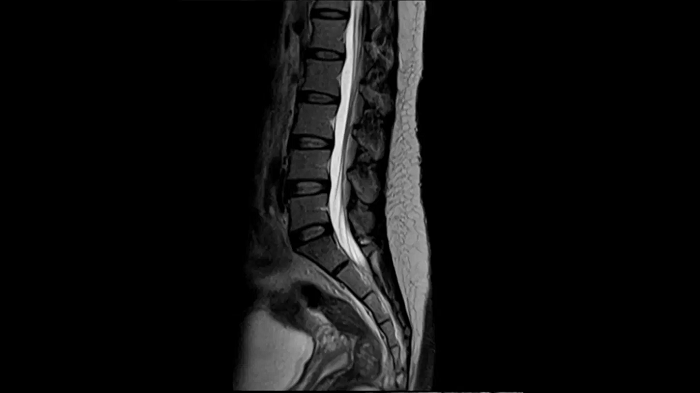

T2 TSE

Ideal depiction of the lower spine with T2 TSE imaging with the use of the Spine Coil.

Deep Resolve Gain & Sharp

0.4 x 0.4 x 4.0 mm2

TA 3:24 minutes

MAC-ID: 7aaaa0215.

MAC-ID: 7aaaa0215. Image Credit: Siemens Healthineers